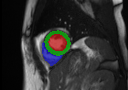

Multi-view segmentation.

The competence of our model to perform end-to-end segmentation across all planes is shown in Table 2 and Fig. 3. Our model not only exhibits comparable quantitative dice scores with nnUNet (that leverages exhaustive parameters tuning) but also shows superior performance over UNETR+ in all regions for both SA/LA planes. This benefit is gained from the learned whole-heart representation. Moreover, the superior performance against SA-only and LA-only segmentation also highlights the significance of integrating multi-view CMR information for more accurate segmentation outcomes.

GTnnUNetUNETR+Ours SA/LA onlyOurs AllRefer to captionRefer to captionRefer to captionRefer to captionRefer to captionRefer to captionRefer to captionRefer to captionRefer to captionRefer to captionRefer to captionRefer to captionRefer to captionRefer to captionRefer to caption

Figure 3: Qualitative segmentation results among nnUNet, UNETR+, and the proposed methods. UNETR+ and the proposed approach in the last column (Ours All) use all sparse CMR sequences as network input, while nnUNet and the second last column (Ours SA/LA) are trained solely with either SA or LA views.